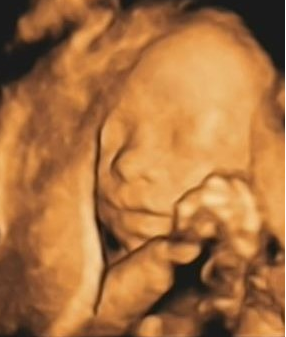

七、超声三维成像:

把二维成像重建成三维图像,也可包括血流的彩色多普勒三维成像。

工作原理:三维超声成像分为静态三维成像和动态三维成像,动态三维成像有时间因素(心动周期)。用整体显像法重建感兴趣区域准实时活动的三维图像,亦称四维超声心动图。静态与动态三维超声成像重建的原理基本相同,均系二维图像的三维重建。